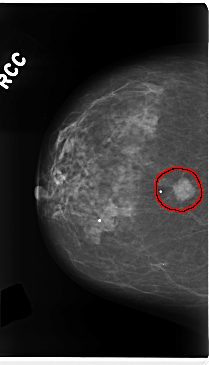

FILE: C_0226_1.RIGHT_CC.OVERLAY

TOTAL_ABNORMALITIES 1

ABNORMALITY 1

LESION_TYPE MASS SHAPE LOBULATED MARGINS SPICULATED

ASSESSMENT 5

SUBTLETY 5

PATHOLOGY MALIGNANT

TOTAL_OUTLINES 1

BOUNDARY